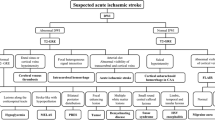

The frontal lobe and cuneus were evaluated as target areas at the basal ganglia level on transverse ASL images. As aforementioned, we chose the cuneus as the target area because of the increased blood flow in the cuneus in MELAS cases. The frontal lobe was selected because it is the region furthest from the cuneus. The console attached to the MRI scanner was used to locate three circular regions of interest (ROIs), each 50 mm2 in size, on both sides of the frontal lobe and cuneus. Regional cerebral blood flow (rCBF) was measured in the ROIs, and the mean value of rCBF obtained from the six ROIs was used in the analysis (Fig. 1). This procedure was performed in all cases in the normal and MELAS groups.

Signal intensity of FLAIR images

The frontal lobe and cuneus on transverse FLAIR images were also evaluated as well as ASL images. A circular ROI of 200 mm2 and oval ROI of 200 mm2 were located on each side of the frontal lobe and cuneus, respectively (Fig. 2a). The signal intensity in the ROIs was measured, and the mean signal intensity was calculated. However, the signal intensities of the frontal lobe and cuneus obtained from the FLAIR images were relative values, unlike rCBF, which is an absolute value. Therefore, the mean signal intensity was normalized to the signal intensity in the brainstem. This is referred to as the normalized signal intensity (nSI). A 180-mm2 circular ROI was located on the brainstem to avoid the effect of cerebrospinal fluid on signal intensity, and the signal intensity in the ROI was averaged for normalization (Fig. 2b).